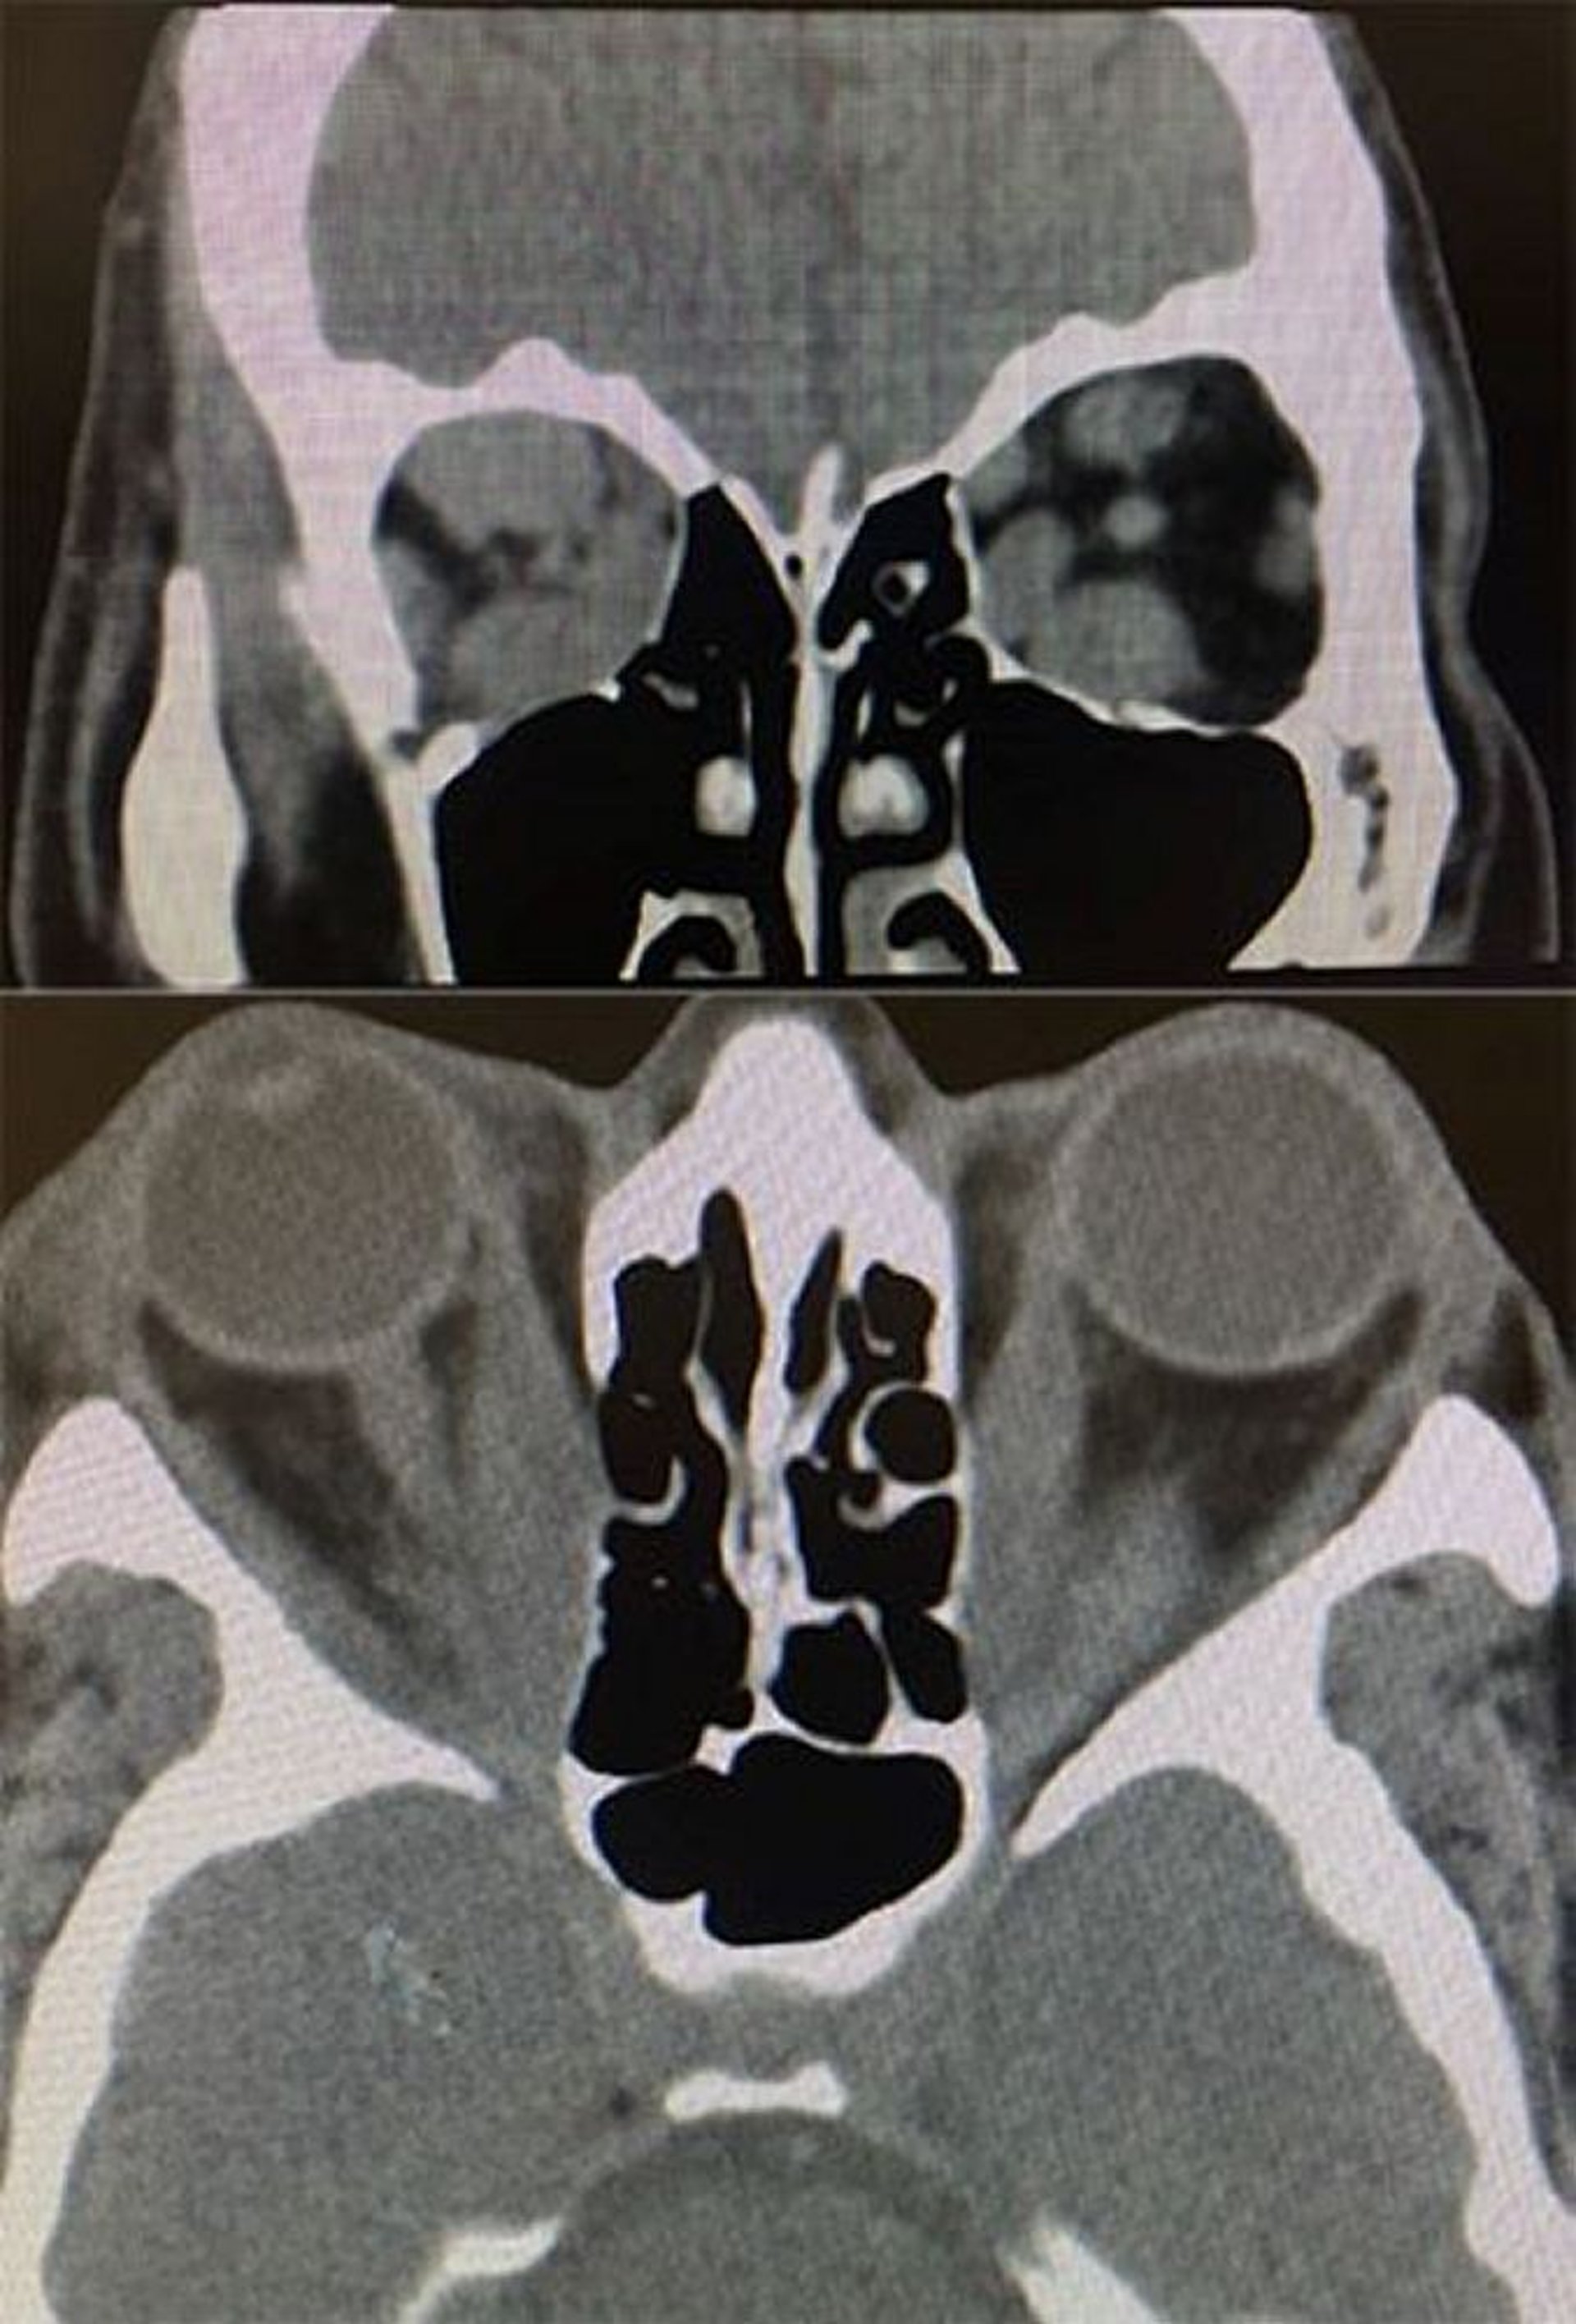

Ендокринна офтальмопатія (КТ)

In this image, axial and coronal CT scans show findings in thyroid eye disease. Bottom: The axial CT scan shows tendon-sparing enlargement of the medial rectus muscle, bilaterally. Top: The coronal CT scan shows enlargement of the inferior, superior, and medial rectus muscles more on the right than left.

Images courtesy of Richard C. Allen, MD, PhD.